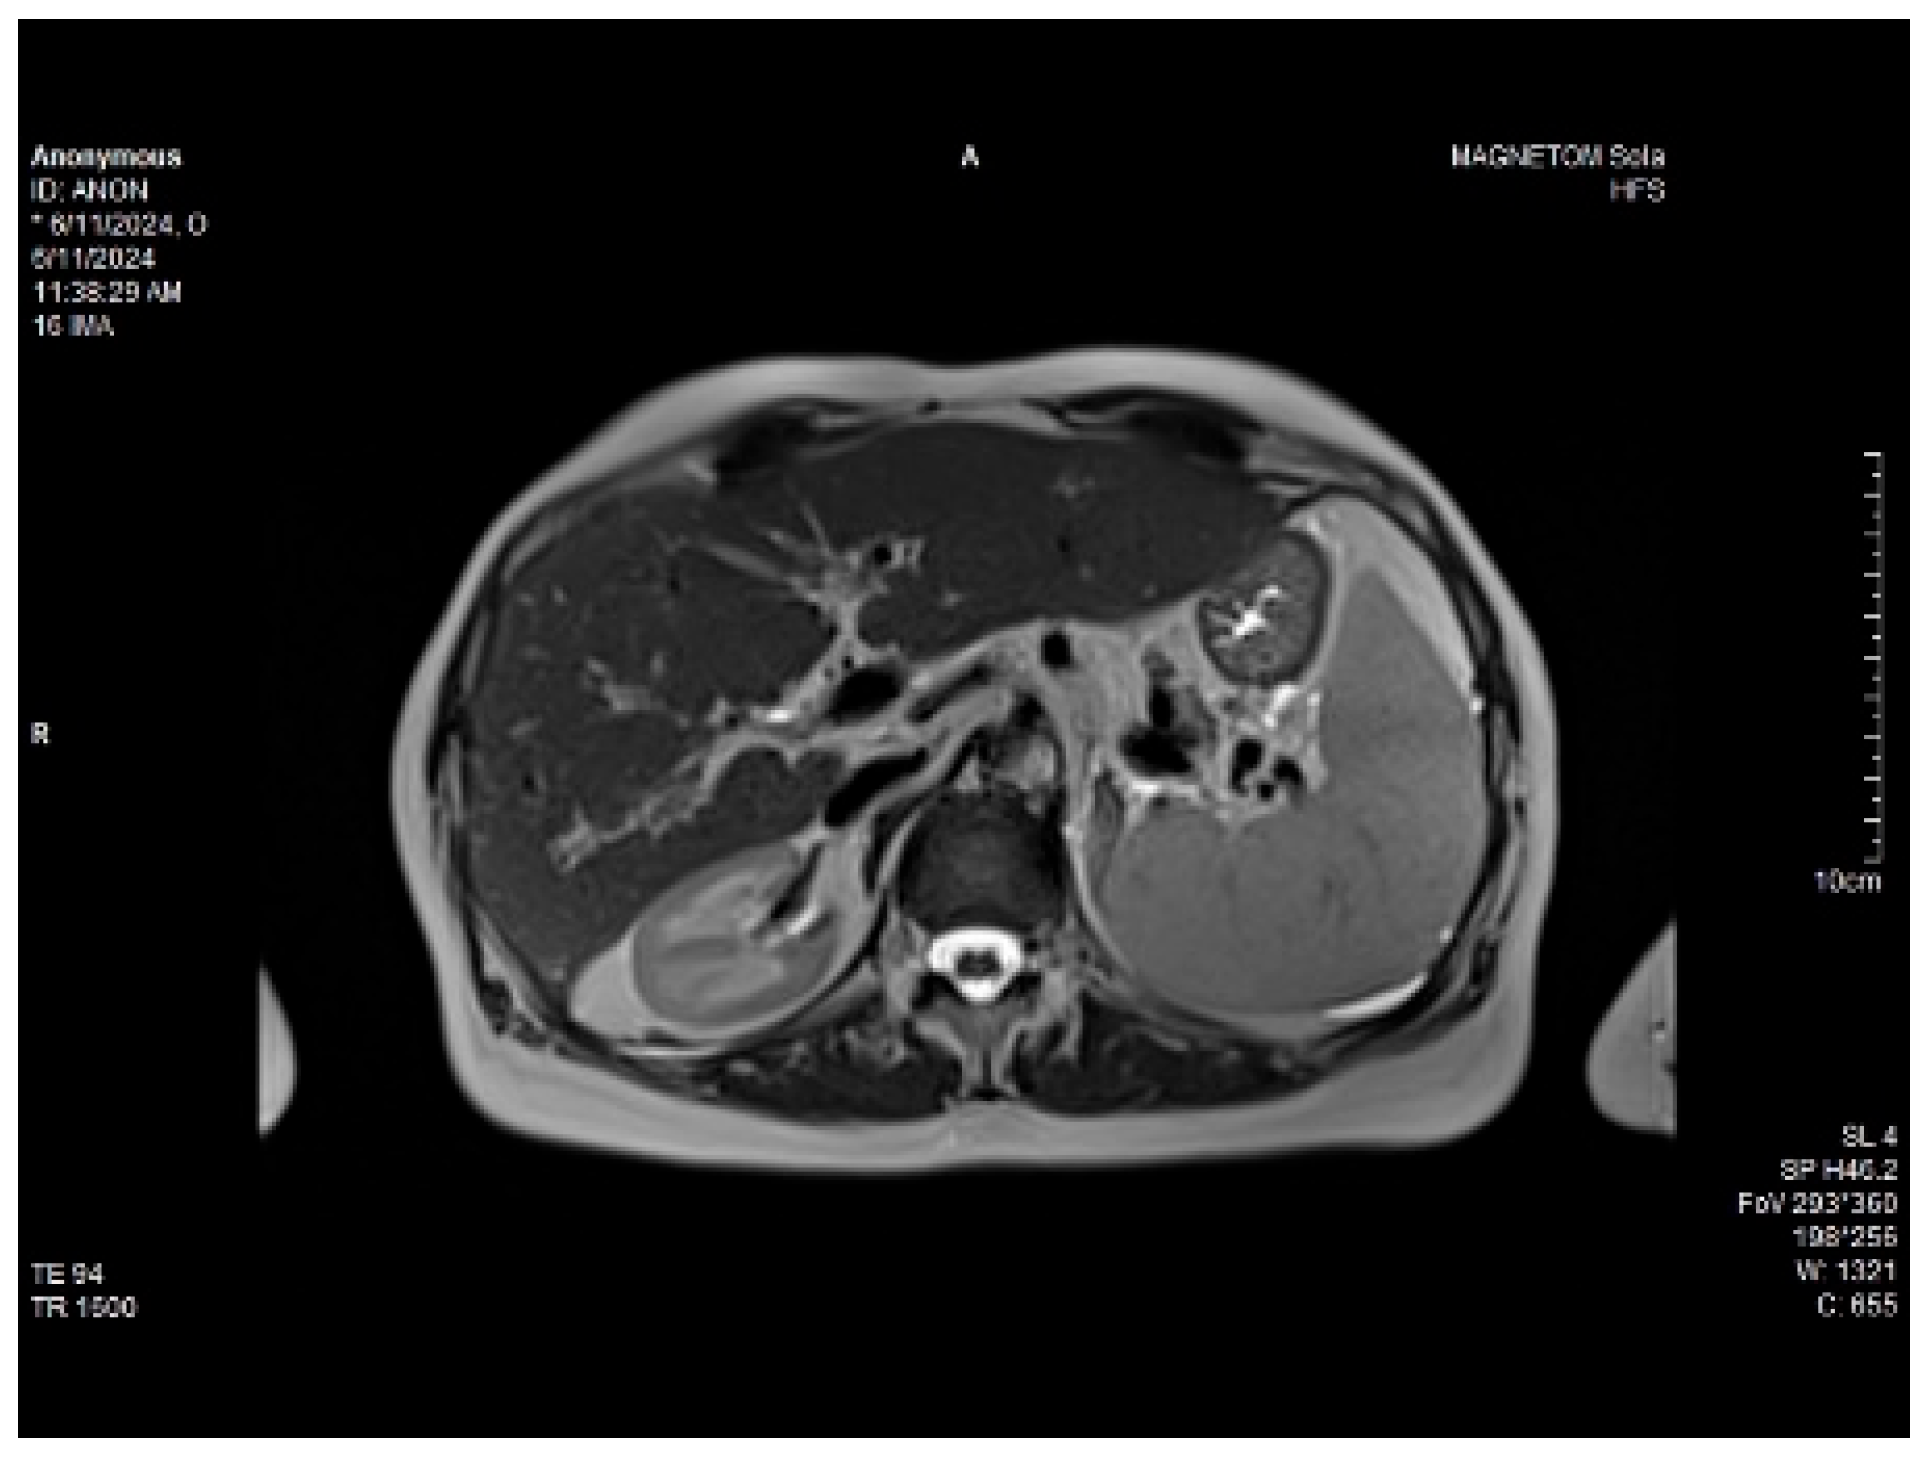

Abdominal MRI study confirmed the hepato-splenomegaly, ascites and the patency of the portal vein system. In addition, small veno-portal shunts were highlighted at the periphery of both hepatic lobes. Various MRI features are depicted in Figure 6, Figure 7, Figure 8 and Figure 9.

Figure 8. Massive thickening of the gallbladder wall, MRI features.